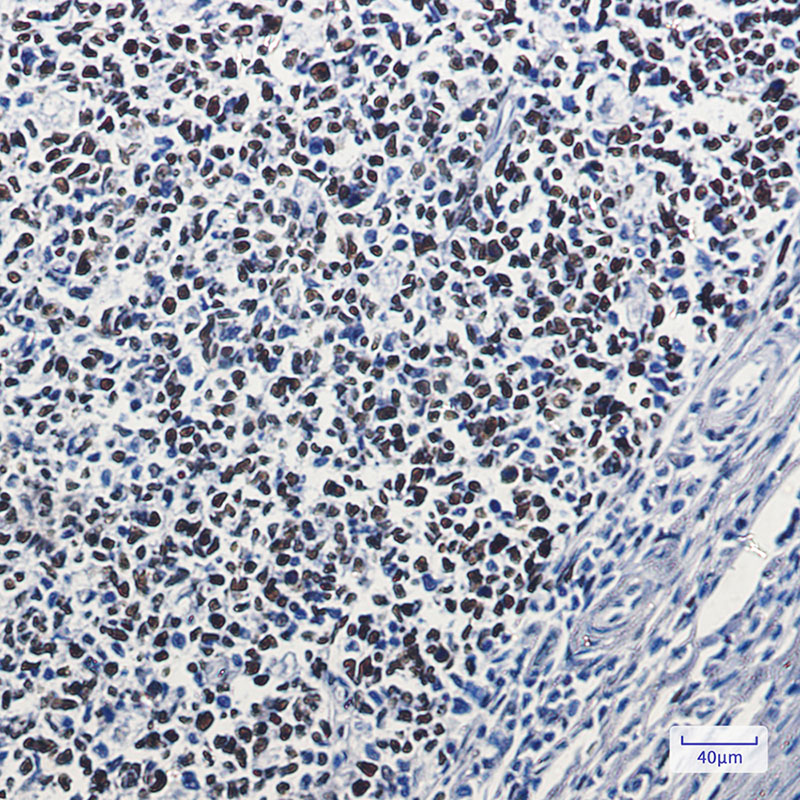

- Immunohistochemistry analysis of paraffin-embedded Human tonsil using MSH6 antibody. High-pressure and temperature Sodium Citrate pH 6.0 was used for antigen retrieval.